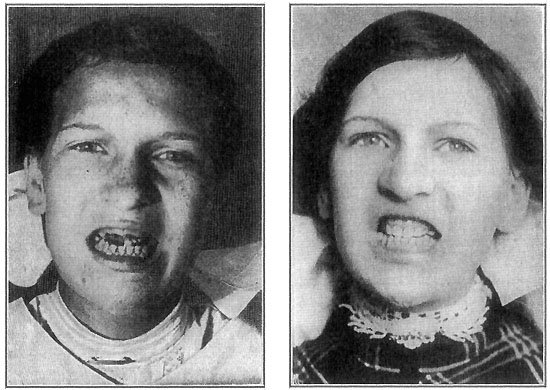

256 Adenoids

257 Mouth-Breathers

Nowadays, in the best dairies, it is required that the barns or sheds in which cows are milked shall have tight walls and roofs and good flooring; that the walls and roofs shall be kept white-washed; and the floor be cleaned and washed be{35}fore each milking, so that no germs from dust or manure can float into the milk. Then the cows are kept in a clean pasture, or dry, graveled yard, instead of a muddy barnyard; and are either brushed, or washed down with a hose before each milking, so that no dust or dirt will fall from them into the milk. The men who are to milk wash their hands thoroughly with soap and water, and put on clean white canvas or cotton overalls, jackets, and caps. As soon as the milk has been drawn into the pails, it is carried into the milk-room and cooled down to a temperature of about forty-two degrees—that is, about ten degrees above freezing point. This is to prevent the growth of such few germs as may have got into it, in spite of all the care that has been taken. Then the milk is drawn into bottles; and the bottles are tightly capped by a water-proof pasteboard disc, or cover, which is not removed until the milk is brought into the house and poured into the glass, or cup, for use.

This method is used in many large dairies to avoid handling the udders or the milk. Its chief drawback is that the long tubes are very difficult to keep clean.